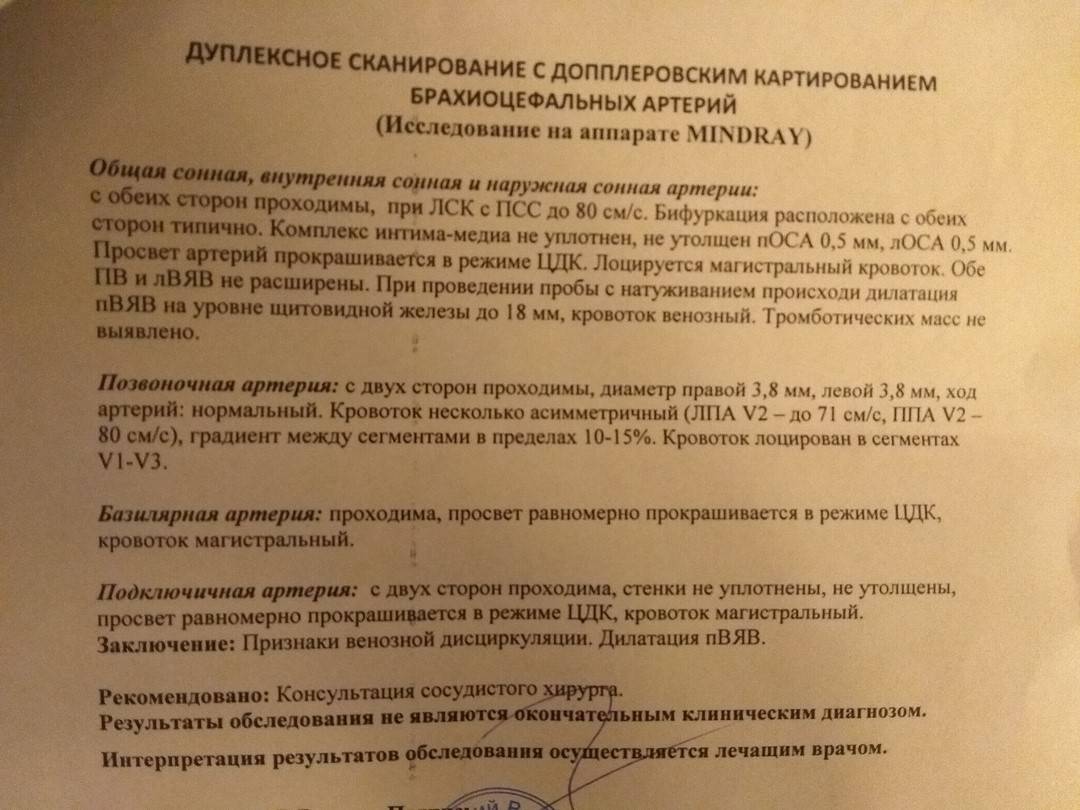

ЦДК сосудов почек: что это и как проводится

Раздел: Фотоэссе